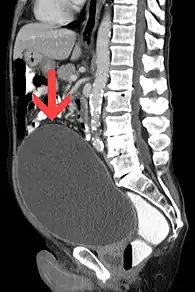

Rétention urinaire aiguë avec vessie très dilatée. | |

La rétention aiguë d'urine est l'incapacité soudaine pour un individu d'émettre des urines alors qu'il a la vessie pleine. Le volume de la vessie augmente alors. On parle parfois ainsi de globe vésical. La capacité de la vessie est importante, mais le volume déclenchant l'envie de miction est d'environ 400 ml pour un adulte.